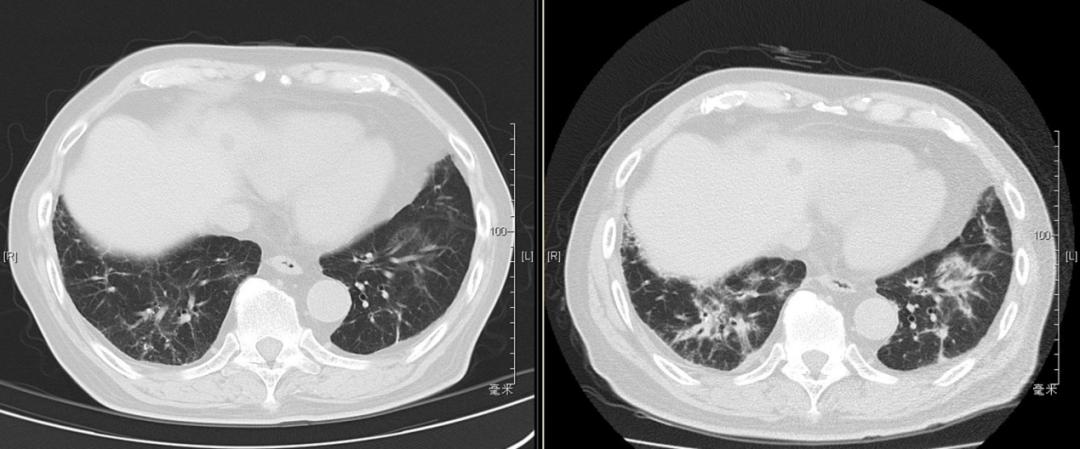

患者于2019年9月24日到我院随访,活动后气促的症状已得到明显改善,胸部CT示双肺间质性炎症灶较前也有明显好转,查动脉血气示PaO2:81mmHg,PaCO2:38mmHg,相较于9月2日的PaO2:65-68mmHg有明显提升。